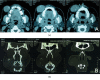

Leiomyomas are rare benign tumors that grow in the tunica media of smooth muscle cells. Leiomyomas occur most frequently in the uterus or gastrointestinal tract and only very rarely in the area of the cheek. This study reports on a rare case of a leiomyoma in the cheek of a 43-year-old woman, who presented with a well-circumscribed, asymptomatic, mobile swelling in the right cheek. This swelling was slightly purplish in color and measured approximately 4 cm × 3 cm. Surgical excision was the treatment of choice, and the diagnosis was based on histopathological and immunohistochemical stains, which were positive for actin and desmin and negative for AE1/AE3, CD34, and S100. The patient's follow-up, two years later, showed no recurrence, and she has been asymptomatic since the surgery.